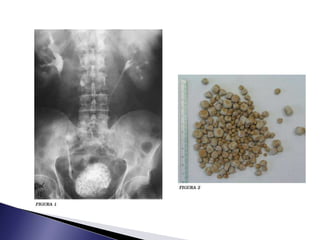

 Rx simple de

abdomen o de la

pelvis puede

mostrar la

presencia de

cálculos.

 La ecografía es el

procedimiento

diagnóstico

definitivo

 Primarios  Seforman dentro de la cavidad vesical  La obstrucción crónica con vejigas dilatadas, con estasis e infección de dicha orina ◦ Tumores prostáticos ◦ Vejigas neurogénica.  La presencia de cuerpos extraños contribuye a la formación de cálculos primarios ◦ Fragmentos de sondas, catéteres con larga permanencia en su interior, suturas no reabsorbible  Secundarios o Migratorio  Es aquel que se forma en el Riñón migra a la vejiga  Presupone una enfermedad obstructiva asociada, ya que si un cálculo pequeño transita por el uréter, librar el cuello vesical y uretra.

 Rx simplede abdomen o de la pelvis puede mostrar la presencia de cálculos.  La ecografía es el procedimiento diagnóstico definitivo